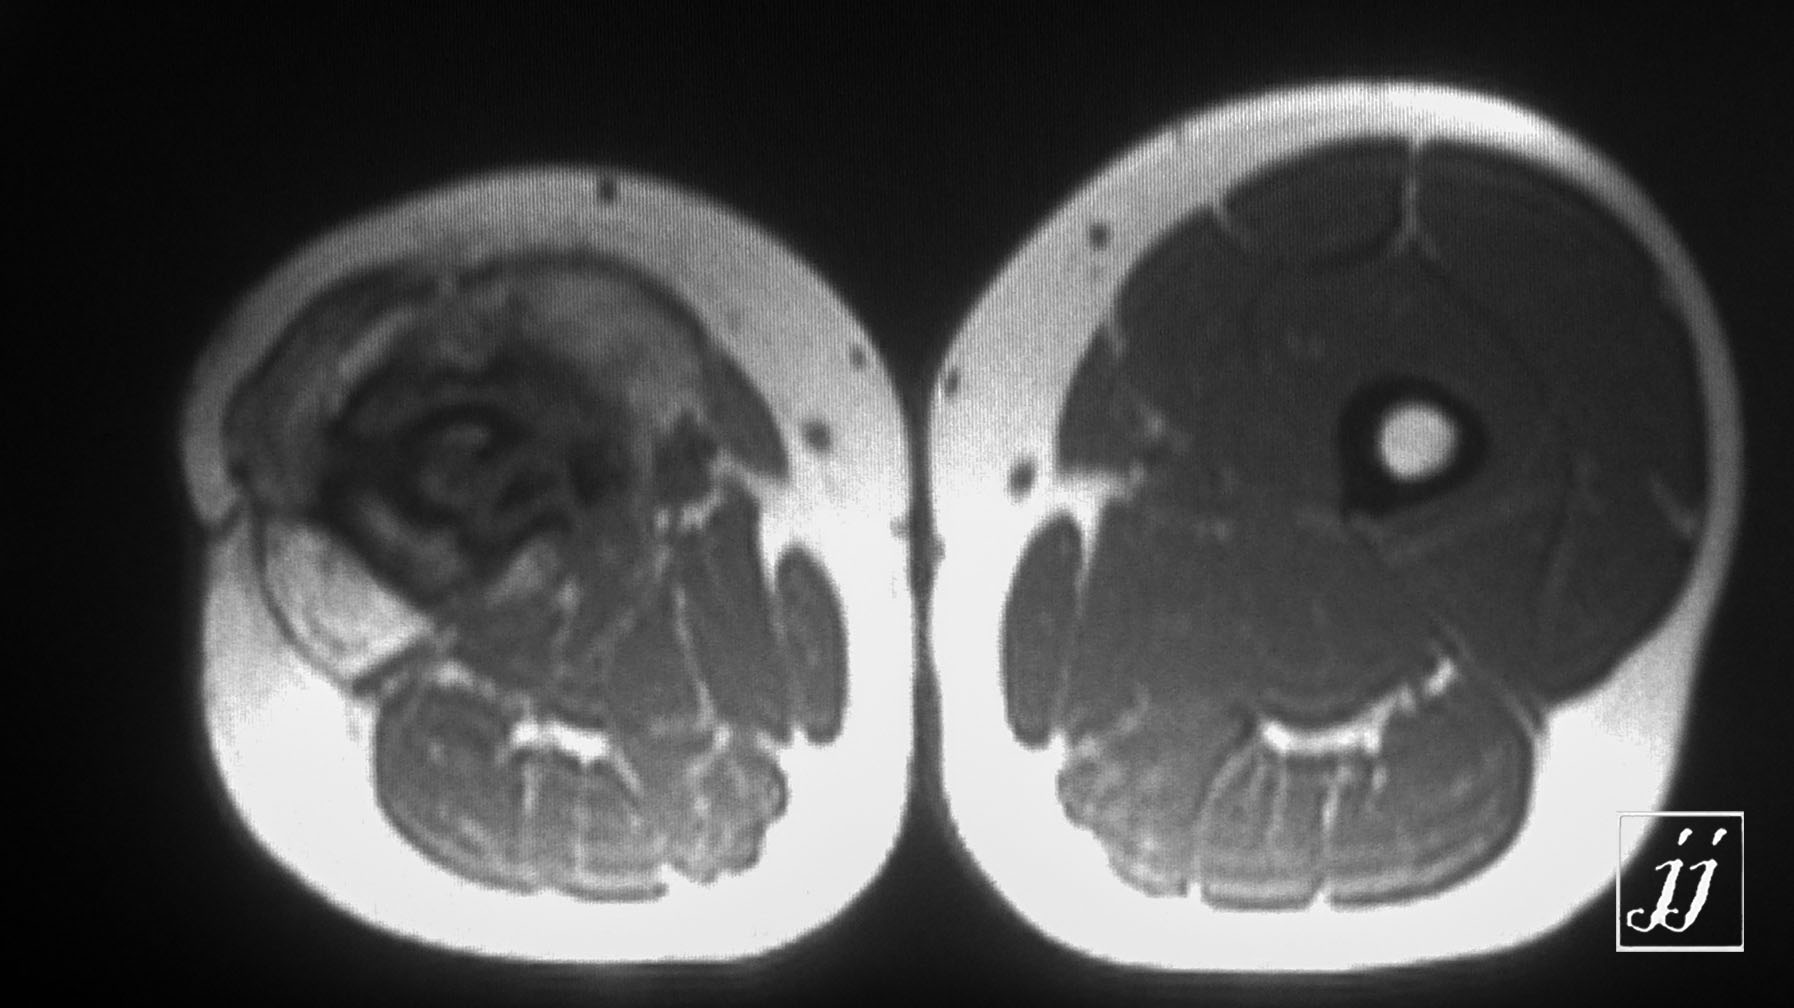

MSK- distal femur lesion that operated before (3)